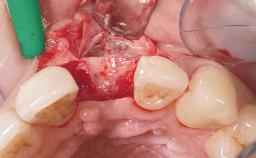

Immediate Flapless Placement of an Implant in a Maxillary Left Central Incisor Site

A 29-year-old female patient presented for treatment to replace the upper left central incisor tooth with an implant- supported restoration. The tooth had been intermittently symptomatic for the previous 12 months. The tooth had originally suffered trauma about 15 years previously. Several endodontic treatments had been performed, including an apicectomy procedure to retain the tooth. The patient was healthy and a non-smoker. She had reasonable expectations in regard to esthetic outcomes and the risk of marginal tissue recession following treatment. At medium smile, the gingival margins of the upper teeth were visible, with a display of 3 to 4 mm of the gingival margins. Gingival recession of tooth 21 and a discrepancy in the gingival levels between teeth 11 and 21 was observable during normal speech and smile.

Socket Integrity Damage to one or more bone walls

Bone Volume Damage to one or more socket walls

Complexity Moderate

Risk of Complications High